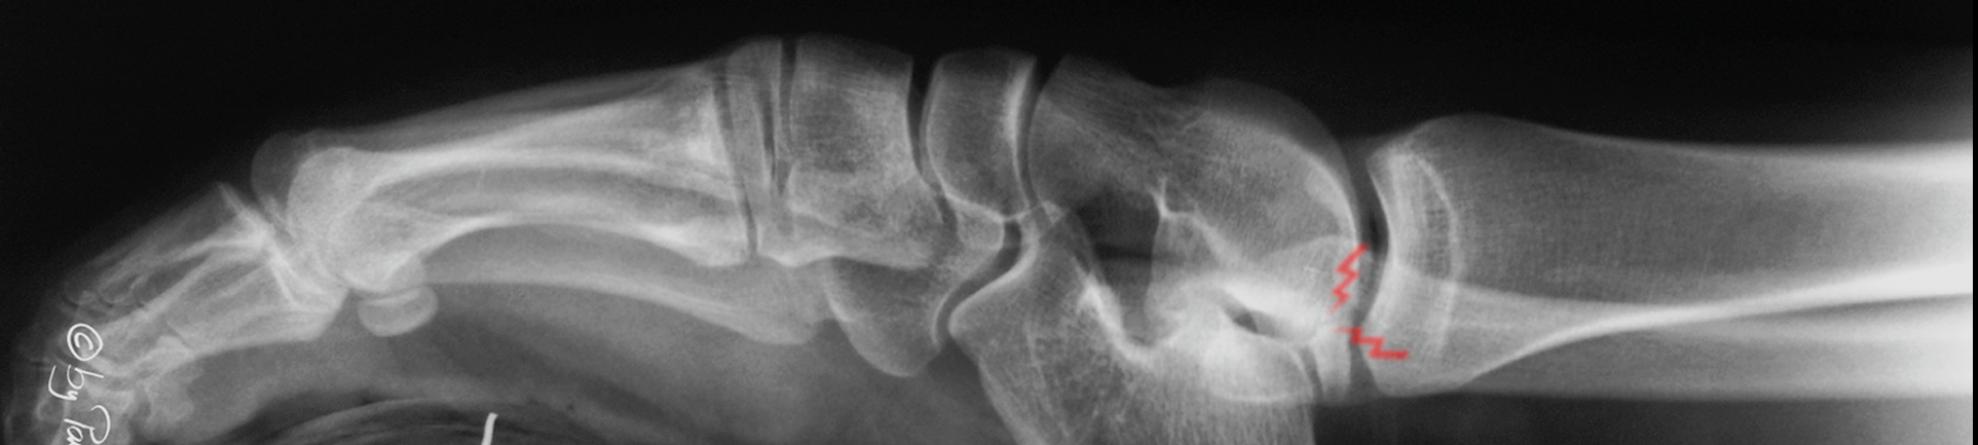

Anterior and posterior impingement with lateral ossicle

37 Years old male with low physical activity and BMI of 32.